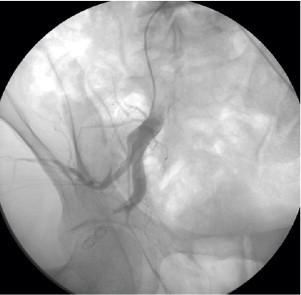

The authors present a case of pseudoaneurysm of the inferior gluteal artery related to an iatrogenic injury due to intramuscular injection of medication, which was treated with selective embolization of the artery during angiography.

The most common manifestation of an inferior gluteal artery pseudoaneurysm is the presence of a painful mass in the buttock that may or may not be associated with neurological symptoms due to compression of the sciatic nerve. Ultrasound with color Doppler and computerized tomography with multi-detectors are useful non-invasive tools for diagnosis. However, both diagnosis and therapy are facilitated by catheter angiography.

作者报告了一例因肌肉注射药物导致医源性损伤引起的臀下动脉假性动脉瘤病例,该病例在血管造影期间通过动脉选择性栓塞进行治疗。

臀下动脉假性动脉瘤最常见的表现是臀部出现疼痛性肿块,该肿块可能与坐骨神经受压导致的神经症状有关,也可能无关。彩色多普勒超声和多排螺旋计算机断层扫描是有用的无创诊断工具。然而,导管血管造影有助于诊断和治疗。